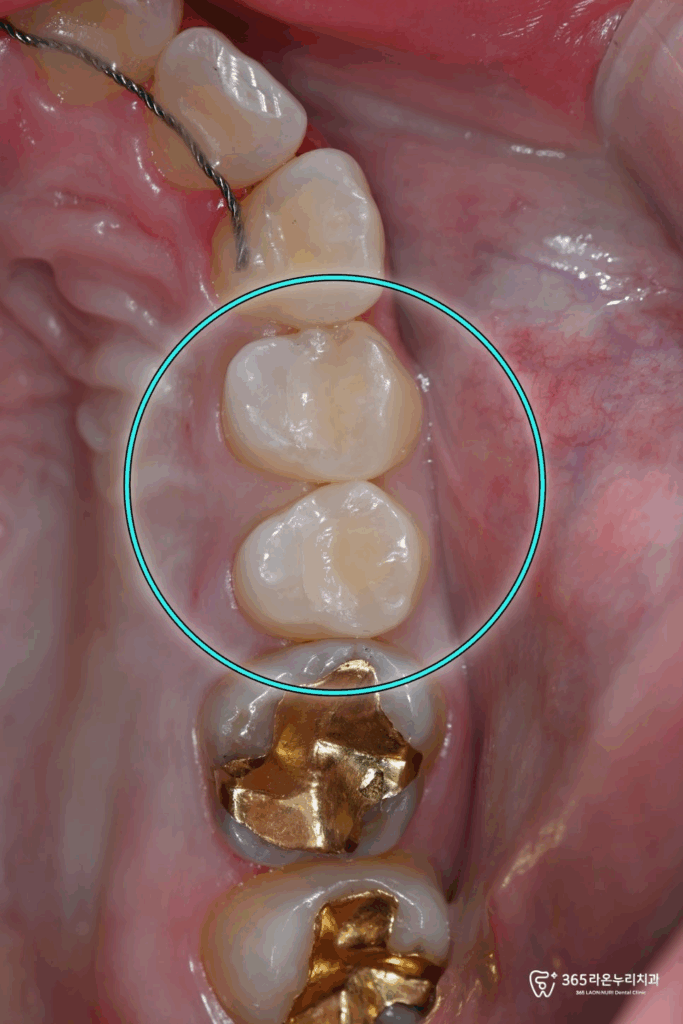

오산대역 치과 에서

먼저 아말감을 제거 충치가 있던

어금니 의 치질을 없앤 뒤

레진으로 수복를 하였으며

치료기간 : 2025.3.13

수복치료를 진행할 때는

심미성을 고려하여 치아색조와 형태,

크기를 개인의 치아에 알맞게 진행하였습니다.

더불어 맞물리는 치아와의 교합을

맞추기 위해 꼼꼼히 조정을 해드렸습니다.